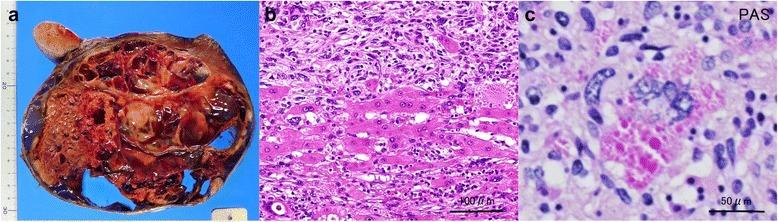

Here, we describe the case of a 65-year-old woman who presented with a huge cystic lesion in the liver. Laboratory studies performed on admission showed modest inflammation, poor nutrition, and elevated levels of total bilirubin, alkaline phosphatase, and γ-glutamyl transferase. Computed tomography showed a well-defined, heterogeneous tumor with multiple cysts involving the right lobe and the medial segment of the liver, with a maximum diameter of 16 cm. Positron emission tomography/computed tomographic scans showed the uptake of 2-(fluorine-18)-fluoro-2-deoxy-D-glucose in a part of the cyst. The patient was diagnosed with mucinous cystadenocarcinoma or sarcoma of the liver and underwent right trisectionectomy. Histopathological studies revealed that the tumor was composed of pleomorphic and polynuclear dyskaryotic cells with eosinophilic globules in the cytoplasm. Mesenchymal hamartoma-like tissue was observed in the peripheral part of the tumor. Immunohistochemical analyses showed the tumor stained with vimentin, α-smooth muscle actin, desmin, α1-antitrypsin, and α1-antichymotripsin. Therefore, a histological diagnosis of UESL was made. Eighteen months following treatment, two recurrent tumors in the remnant liver were detected and resection of the recurrent tumors was performed.

在此,我们描述一例65岁女性,其肝脏出现巨大囊性病变。入院时进行的实验室检查显示有轻度炎症、营养不良,总胆红素、碱性磷酸酶和γ-谷氨酰转移酶水平升高。计算机断层扫描显示一个边界清晰、不均匀的肿瘤,有多个囊肿累及肝脏右叶和肝中叶,最大直径为16厘米。正电子发射断层扫描/计算机断层扫描显示囊肿部分摄取2-(氟-18)-氟-2-脱氧-D-葡萄糖。该患者被诊断为肝黏液性囊腺癌或肉瘤,并接受了右半肝切除术。组织病理学研究显示肿瘤由多形性和多核异核细胞组成,细胞质中有嗜酸性小球。在肿瘤周边观察到间叶性错构瘤样组织。免疫组织化学分析显示肿瘤细胞波形蛋白、α-平滑肌肌动蛋白、结蛋白、α1-抗胰蛋白酶和α1-抗糜蛋白酶染色阳性。因此,做出了UESL的组织学诊断。治疗18个月后,在残余肝脏中检测到两个复发肿瘤,并对复发肿瘤进行了切除。